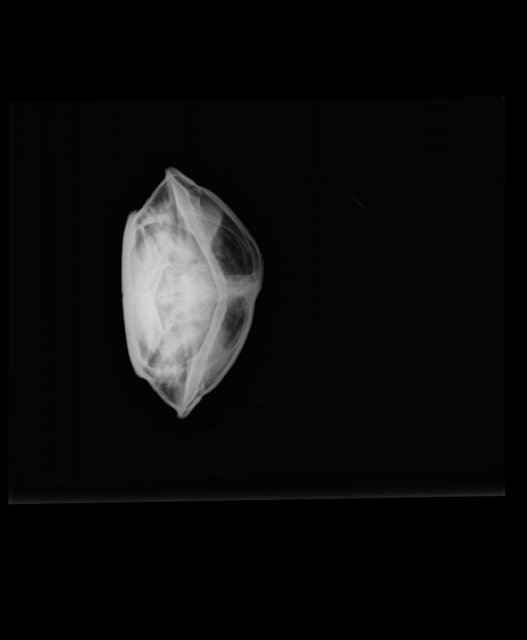

Характерное потемнение в правой части туловища на рентгеновском снимке

Около 2 месяцев назад на панцире появилось что-то вроде затертости/царапины на панцире. Подумали, что проблема в недостатке кальция, либо, возможно он упал с суши/поцарапался, ничего не подозревая свозили на рентген, чтобы предупредить различные другие проблемы. Снимок показал это. Вряд-ли пневмония, условия для неё не подходящие, да и признаков болезни черепаха не выказывала. Чувствует себя чепик нормально, от еды не отказывается, в воде плавает, на суше тоже сидит. Ветеринар сказал, что внутри нечто больше похожее на воздух, чем на жидкость и находится оно не в лёгких. Подскажите, пожалуйста, в чем проблема, как лечить, связано ли это с царапиной на панцире?

IMG_20240126_173900_526_edit_608459165666483.jpg